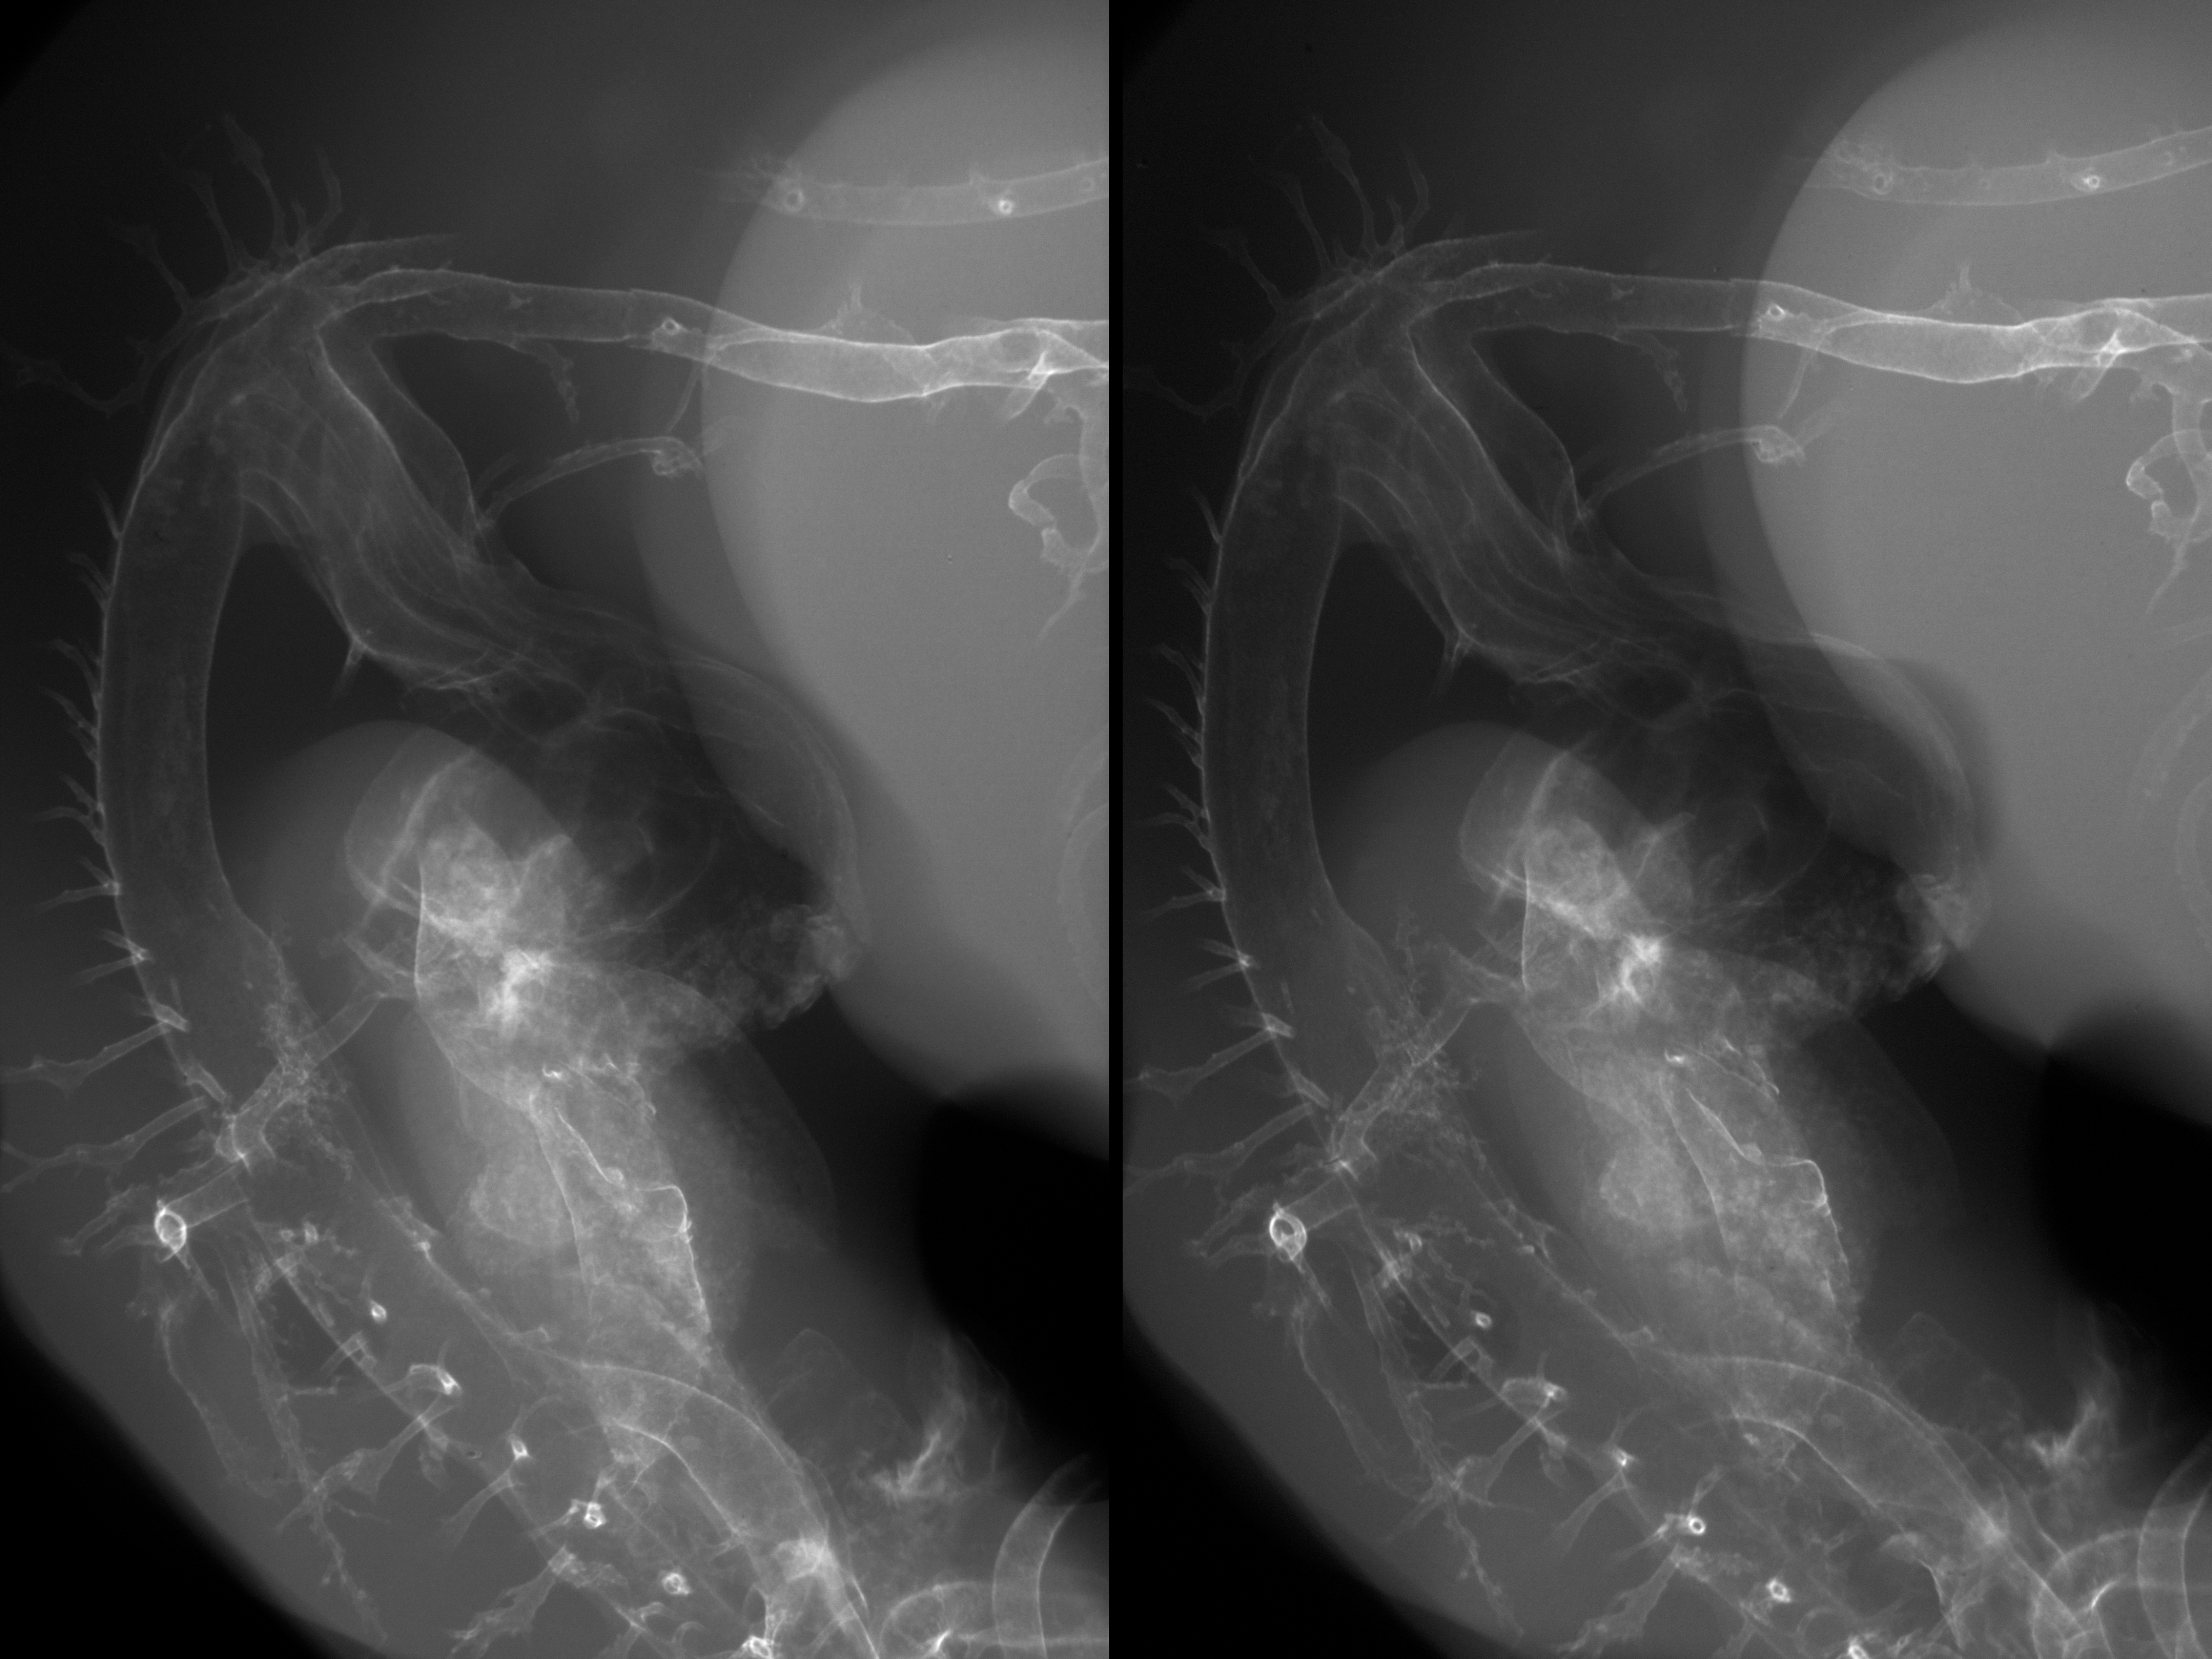

Chick Embryo Microangiography

Hamburger-Hamilton (HH) Stage 27 (approx. 5 - 5.5 days)

Stereo X-Ray Micrographs